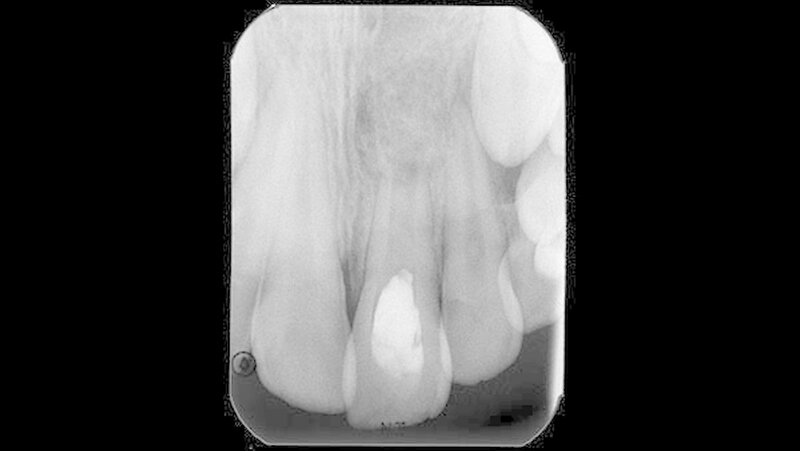

Weitere Verletzungen waren nicht vorhanden. Da sich der Unfall während eines Urlaubsaufenthalts ereignet hatte, erfolgte die Erstversorgung durch einen Zahnarzt vor Ort. Der gesunde Patient wies zu diesem Zeitpunkt ein altersentsprechendes Wechselgebiss auf. Im Zusammenhang mit der Erstversorgung wurde ein Zahnfilm (Abbildung 1) angefertigt.

Fokussiert auf den betroffenen Zahn 21 zeigte dieser ein nicht abgeschlossenes Wurzelwachstum und ließ eine unfallbedingte Schmelzabsplitterung an der Inzisalkante erkennen. Eine Wurzelfraktur am betroffenen Zahn sowie eine Alveolarknochenfraktur ließen sich auf der angefertigten Aufnahme nicht vermuten. Da es zu keinen weiteren Beschwerden und einem komplikationsfreien Verlauf kam, stellte sich der Patient zu keiner weiteren Kontrolluntersuchungen beim Zahnarzt am Heimatort vor.